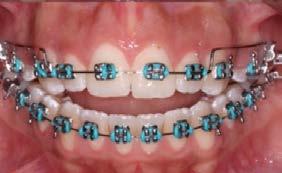

Caso clínico: paciente femenino de 19 años, patrón dolicofacial, perfil convexo, clase II esqueletal debido a una retrusión mandibular, mordida abierta anterior esqueletal, clase II molar, clase canina no establecida por mordida abierta, apiñamiento severo superior e inferior y deglución atípica.

Resultados: obtención de una clase canina I y clase molar II funcional, se corrigieron las sobremordidas horizontal y vertical, y se logró la coincidencia de líneas medias facial y dental. El manejo de la mordida abierta anterior se llevó a cabo por medio de la corrección del hábito de deglución atípica con la ayuda de spikes de resina, elásticos intermaxilares y arcos utility, y se obtuvieron buenos resultados estéticos, dentales y funcionales.